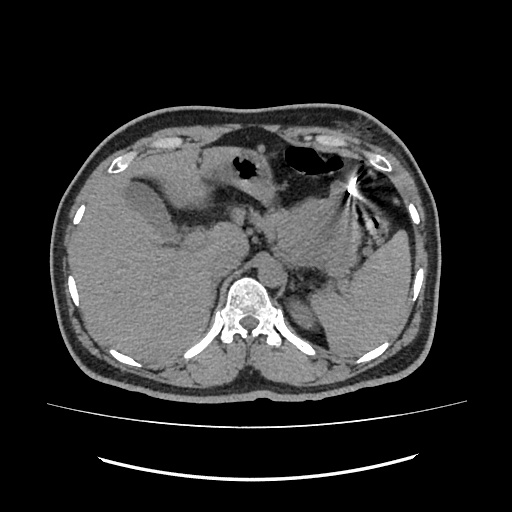

PANCRATIC BIOPSY, 34Y M